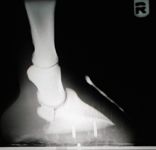

The major concern of any fracture repair is to maintain adequate stability for fracture healing to occur. The stability provided by open reduction and internal fixation (ORIF) is difficult to achieve with other methods of fracture repair. However, ORIF invades the fracture site, can lead to further disruption of vasculature and soft tissue and may provide a mechanism for infection to develop or persist.